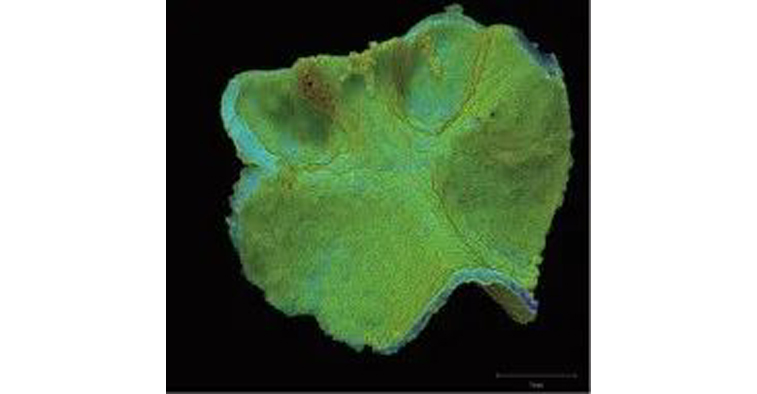

图10~14显示小鼠股骨皮质骨、骨小梁及皮质骨内血管的扫描结果,图像处理为某软件公司的TRI/3D-Bon骨结构分析软件。

图10 白色:皮质骨和骨小梁

红色:皮质骨中的血管

绿色:生长板软骨

图11 白色:骨小梁

图10、11中白色为皮质骨和骨小梁、红色部分为皮质骨中的血管、绿色部分为生长板软骨,图10中皮质骨在外观上是半透明的。

图14 皮质骨和骨小梁厚度的测量

图13是提取的成长板软骨。图14是对提取的皮质骨和骨小梁测量出的厚度结果,从外观上使用不同颜色标示出各不相同的薄、厚部分。